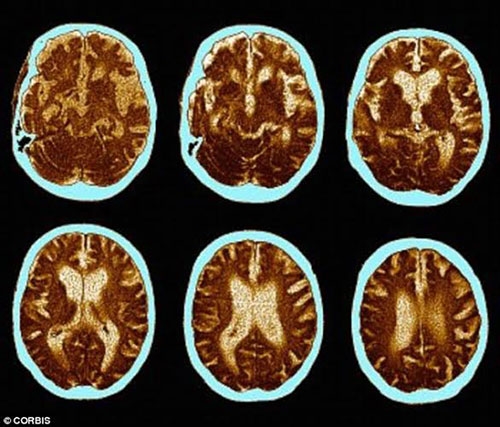

Ngăn chặn chứng mất trí nhớ

Chúng ta đều biết rằng sự số lượng của tế bào não tỷ lệ nghịch với số tuổi. Thực tế, khi bắt đầu bước vào tuổi 35, mỗi ngày, chúng ta mất 7.000 tế bào não. Đọc thông tin này khiến nhiều người rất lo lắng và bi quan.

| Nghiên cứu của Trường Đại học Princeton cho thấy sex thường xuyên giúp chúng ta sản sinh những tế bào não mới. |

Các yếu tố như căng thẳng và trầm cảm có thể thu nhỏ vùng hippocampus, trong khi tập thể dục và quan hệ tình dục lại có tác dụng ngược lại.

“Những người lớn tuổi có ít hoạt động tình dục có nguy cơ mất trí nhớ cao”, Tiến sĩ Ghosh, chuyên gia về sức khỏe tình dục tại Bệnh viện Spire, Liverpool (Anh) cho biết.

Không những thế, chuyện phòng the cũng tăng lưu lượng máu đến não, cải thiện mức độ oxy.

“Quét não bằng kỹ thuật cộng hưởng từ (MRI) đã cho thấy đạt cực khoái giúp các tế bào thần kinh trong não hoạt động mạnh hơn và sử dụng nhiều oxy hơn”, Barry Komisaruk, Giáo sư tâm lý học tại Đại học Rutgers giải thích.